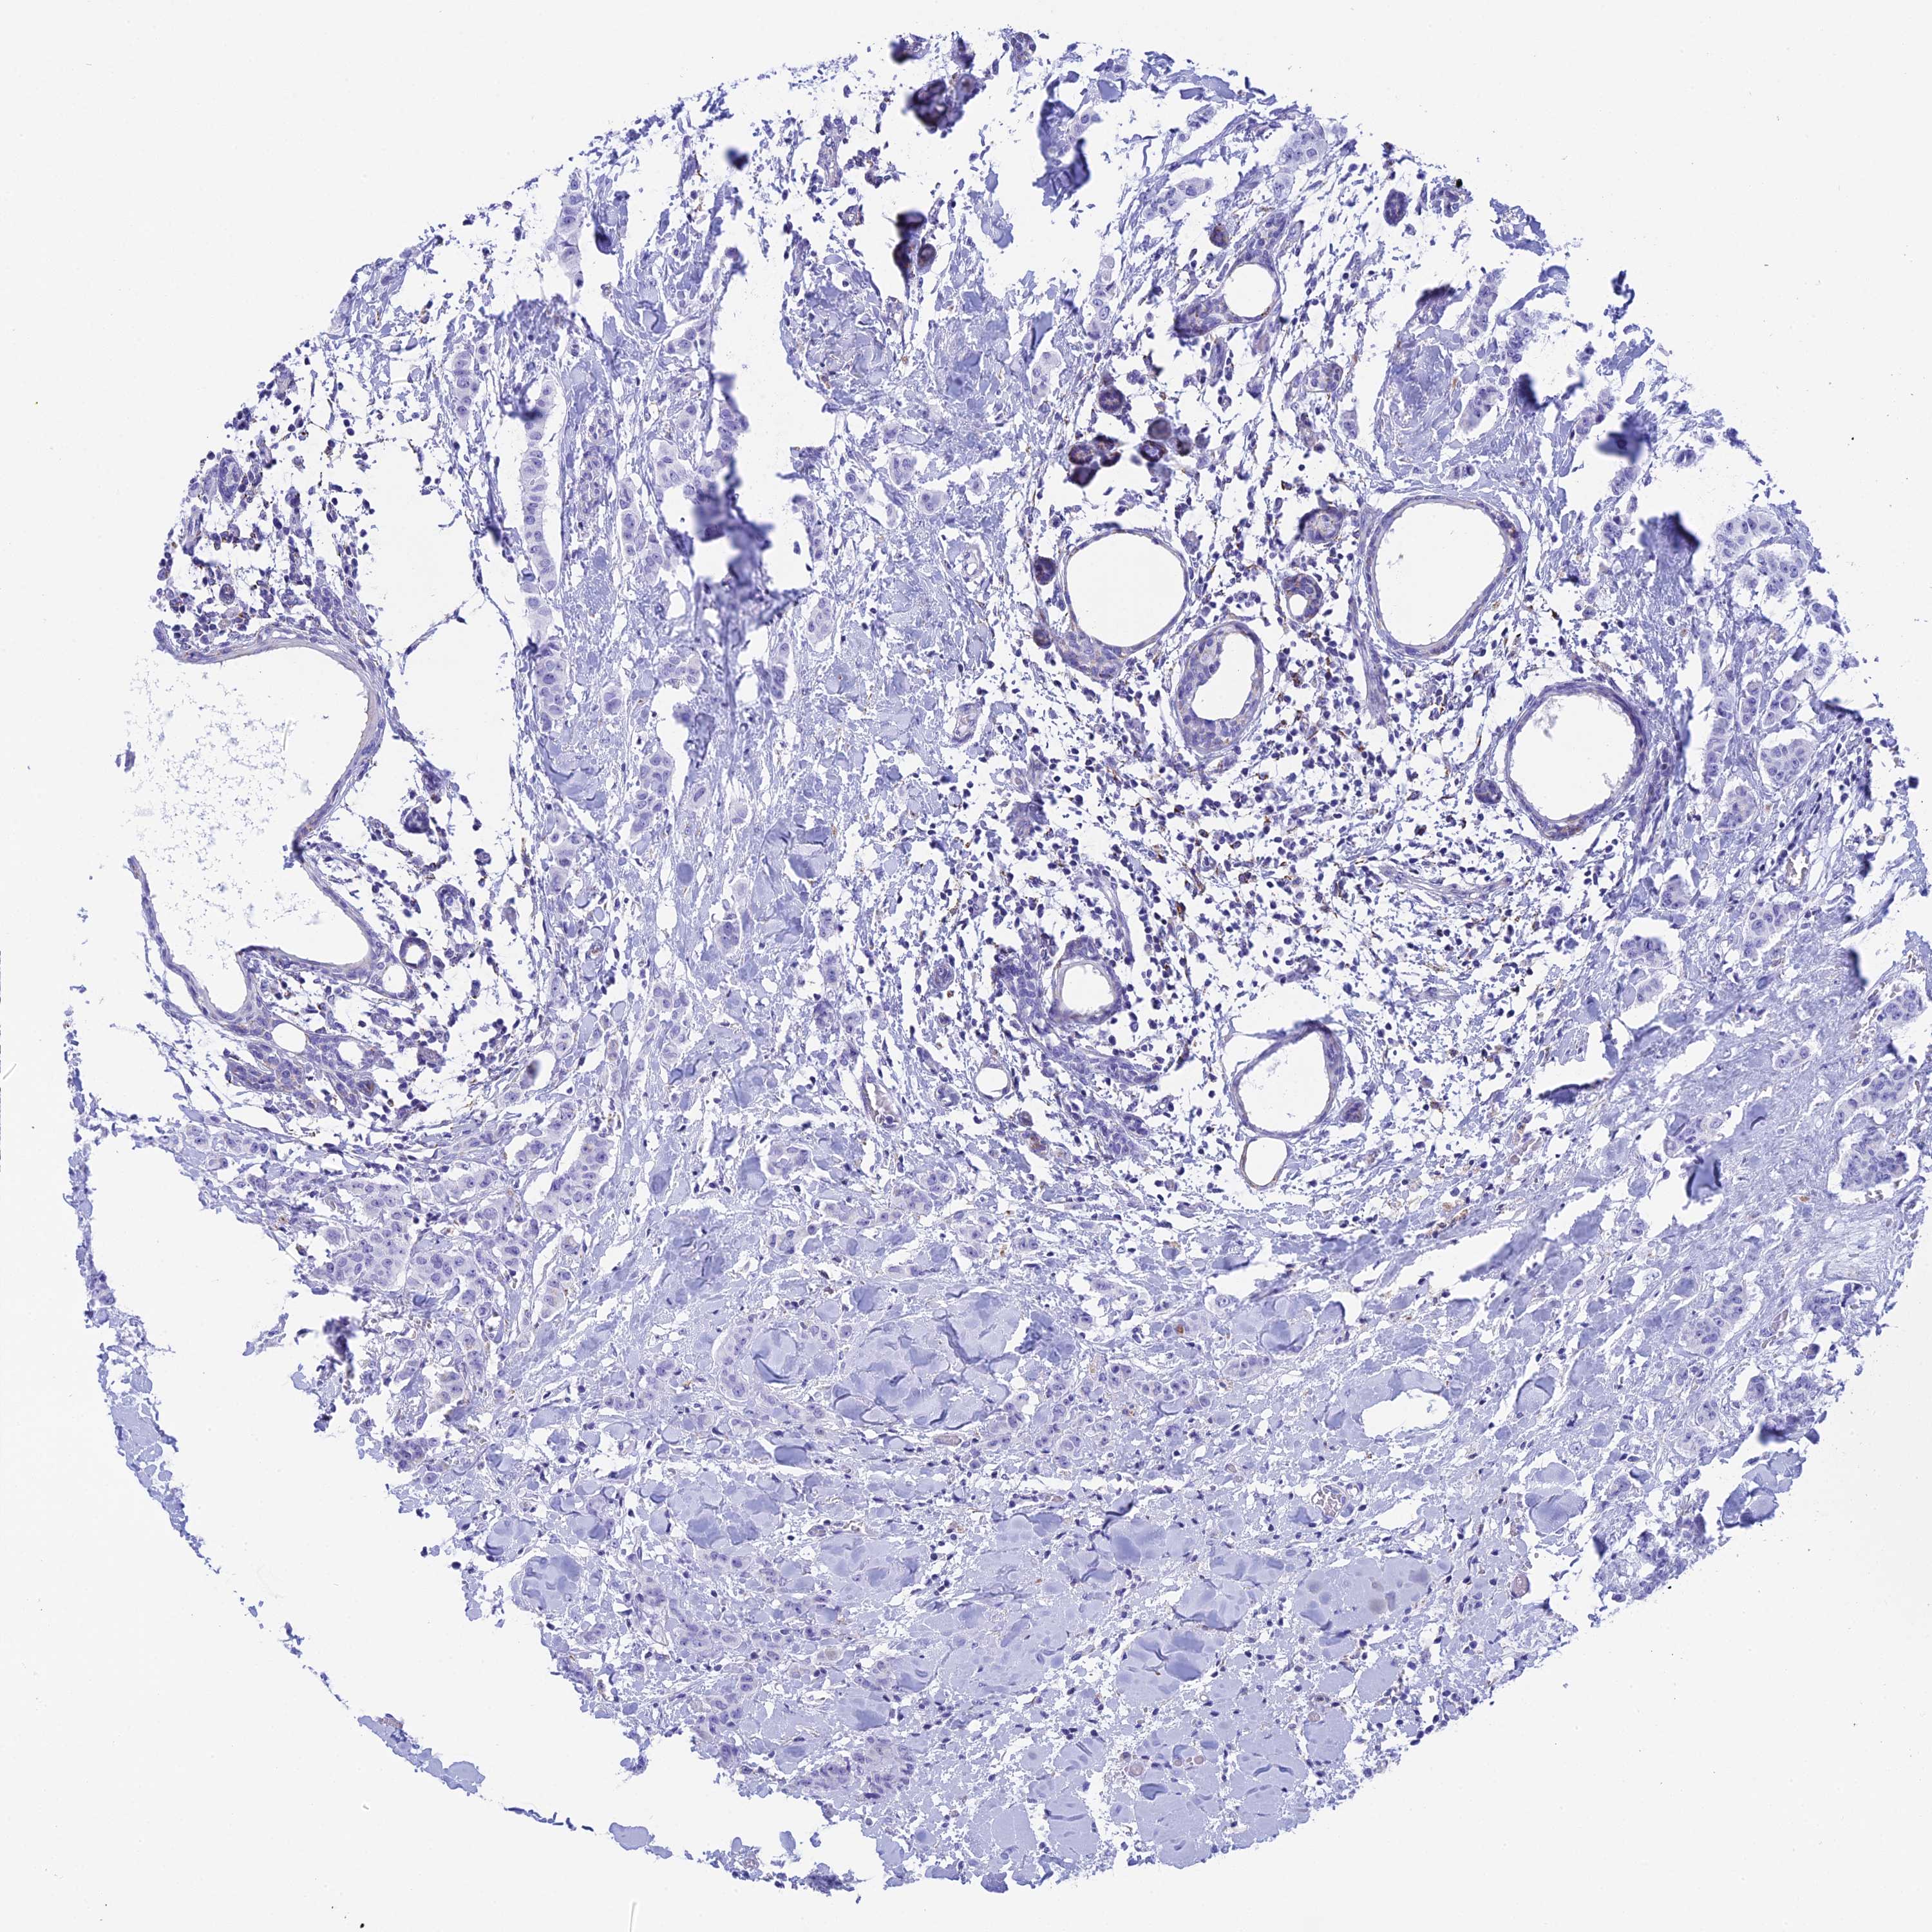

CANCER BREAST CANCER Show tissue menu

BRCA TCGA BRCA VALIDATION PROTEIN EXPRESSION

Breast cancer

Human cancer

IL17B is potential prognostic, high expression is favorable in Breast Invasive Carcinoma (TCGA)